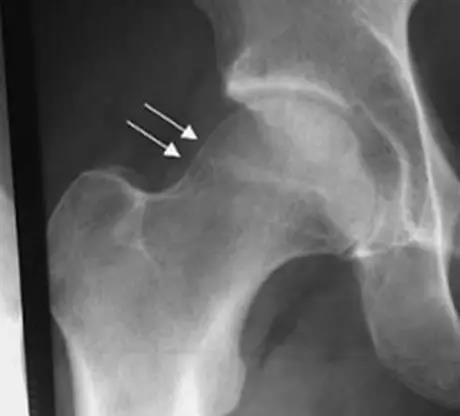

凸轮撞击型FAI▼

- 股骨头颈联合处前上缘骨性突起。

- 非圆形的股骨头。

- 股骨头颈联合处前缘骨性突起、骨质硬化,α角增大。

- 凸轮撞击型FAI--并盂唇撕裂。